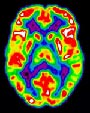

(cc)Institut Douglas

La neuroéthique, une nouvelle frontière pour les sciences humaines

À propos de : B. Baertschi, La neuroéthique : ce que les neurosciences font à nos conceptions morales. et K. Evers, Neuroéthique : quand la matière s’éveille.

par Stanislas Dehaene [06-10-2009]

Que nous enseigne la science du cerveau sur nos jugements et nos comportements moraux ? Deux livres traitent la question en présentant une discipline nouvelle : la neuro-éthique.